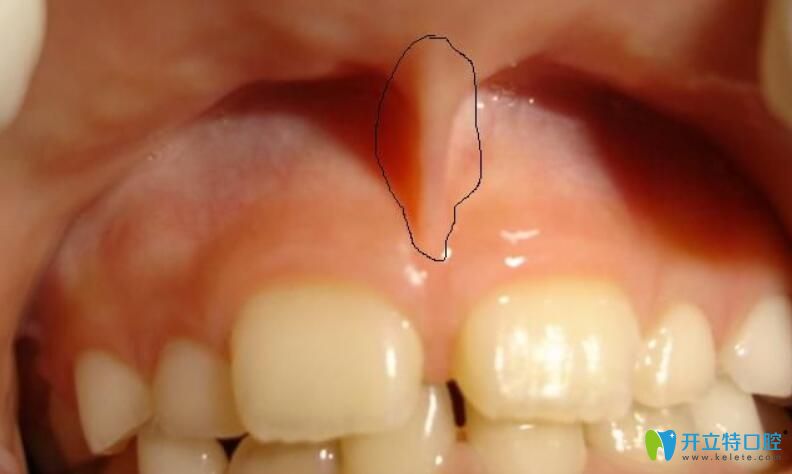

10、多生牙

任何牙位都可能萌生多生牙,不過多生牙較長在的位置是上門牙間有多余,多生牙多為畸形牙,它們占據(jù)了正常牙的位置,會(huì)致使這些正常的牙齒出現(xiàn)錯(cuò)位或萌出障礙。

多生牙